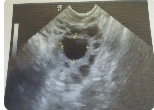

在受精卵成功着床后约5-6周时,会出现孕囊的迹象。此时,在B超检查中可以看到一个小小的液体囊泡,并且可以听到心跳声。如果您没有出现任何流血或其他健康问题,则可以在4到7周内进行第一次B超检查。

在第一次B超检查中,医生将使用阴道探头进行内部扫描来确定孕囊的大小和位置。孕囊通常会在子宫内形成,并且可以清晰地看到其轮廓和形状。同时医生还会检查是否有多个孕囊或其他健康问题。

在受精卵成功着床后约5-6周时,可以开始看到孕囊。如果您想确定胚胎是否已经成功着床并形成孕囊,则需要通过B超检查来确认。在第一次B超检查中,医生将使用阴道探头进行内部扫描来确定孕囊的大小和位置。